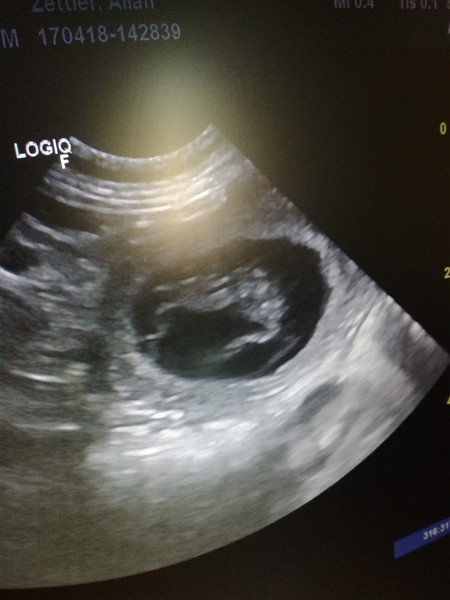

Hurra, wir sind schwanger, wie das Ultraschallbild beweist

Ein kleiner CäsAliah-Astronaut